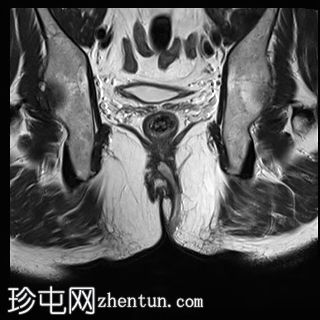

矢状位

T1时间

位于5点钟和6点钟位置之间,在STIR和T2加权图像上呈高信号。

瘘管起源于括约肌间平面附近,穿过肛门内外括约肌,并延伸至左侧坐骨肛门窝。瘘管内充满液体信号,周围有轻微水肿。肛提肌上方未观察到颅骨延伸。

根据圣詹姆斯大学医院的磁共振分类系统,该病例被归类为III级左侧肛周经括约肌瘘,左侧坐骨肛门窝可见炎症改变。